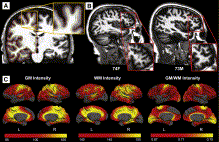

Shape Based Level SegmentationThis class of algorithms explicitly manipulates the representation of the object boundary to fit the strong gradients in the image, indicative of the object outline. Bias in the boundary evolution towards the likely shapes improves the robustness of the segmentation results when the intensity information alone is insufficient for boundary detection. More... New: Salat D.H., Lee S.Y., van der Kouwe A.J., Greve D.N., Fischl B., Rosas H.D. Age-associated alterations in cortical gray and white matter signal intensity and gray to white matter contrast. Neuroimage. 2009 Oct 15;48(1):21-8.